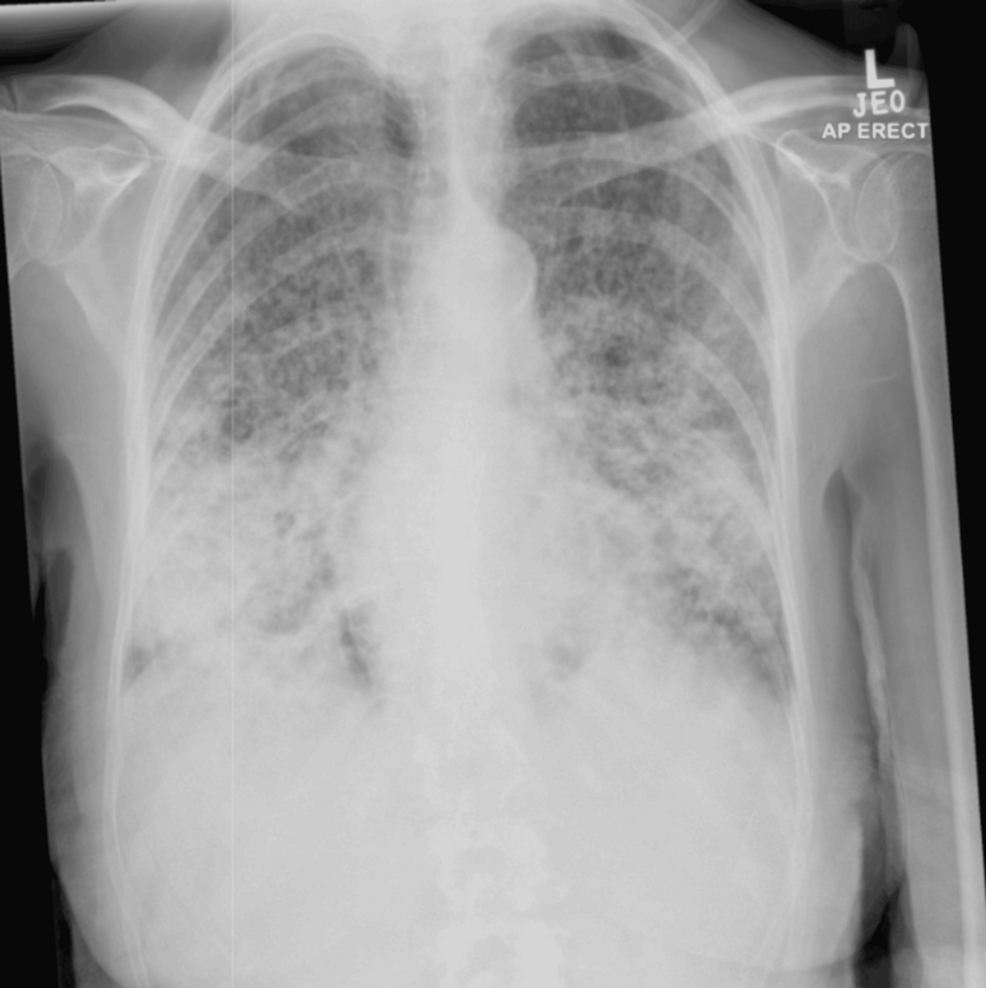

病史摘要:33 岁女性,无吸烟饮酒及特殊家族史,因“活动后胸闷、气短”于 2020 年 9 月 4 日就诊。胸部高分辨率 CT 提示左下叶基段肿块阴影伴左肺散在小结节。心包积液和胸腔积液涂片、支气管镜病理均证实为左下叶基底段腺癌,基因检测示 EGFR 外显子 19 突变和 TP53 突变,临床诊断左肺腺癌(T3N3M1a IVA 期,EGFR ex19del+,TP53+)。 诊疗过程:一